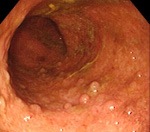

Количество и размеры псевдополипов при псевдополипозе ободочной кишки существенно варьируют. У одних больных выявляются единичные узлы, у других - множественные образования, покрывающие значительную часть слизистой оболочки сигмовидной кишки. Средний диаметр узла при псевдополипозе ободочной кишки составляет 5-10 миллиметров, при этом отдельные псевдополипы могут достигать 5 и более сантиметров. С учетом внешнего вида узлов различают обычные псевдополипы, образования в форме шапочки и глубокий кистозно-полипозный колит.

В процессе изучения морфологической структуры образований, возникающих у больных псевдополипозом ободочной кишки, определяется неизмененный эпителий, разрастания эпителия или грануляционная ткань. При исследовании слизистой оболочки, пораженной язвенным колитом выявляются расширенные капилляры, кровоизлияния, язвы и крипт-абсцессы. Подслизистый слой обычно изменен незначительно. Слизистая оболочка кишечника у пациентов с болезнью Крона грубая, бугристая, по внешнему виду напоминает «булыжную мостовую».